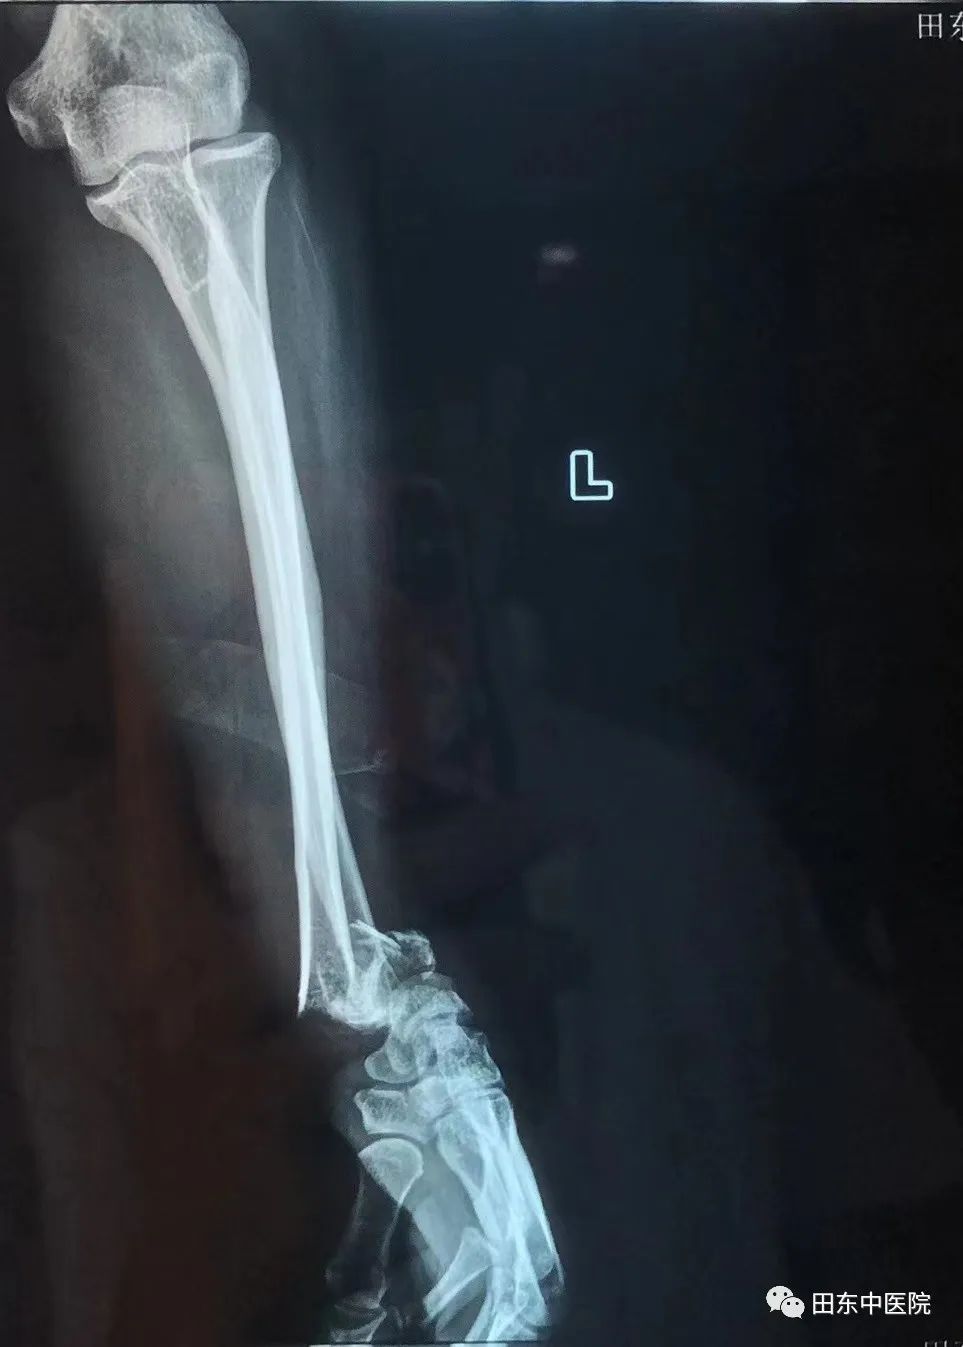

48岁的李叔(化名)从1.2米的施工凳子上不慎坠落导致左腕部肿胀、畸形,在家人的陪同下来到我院骨伤科就诊,经拍片检查后诊断为:左尺桡骨远端开放性骨折并尺桡腕关节半脱位。接诊的医生看过后,向骨伤科二区农达杰主任汇报病情,农主任决定为其行手法复位治疗。

▲左尺桡骨远端开放性骨折并尺桡腕关节半脱位